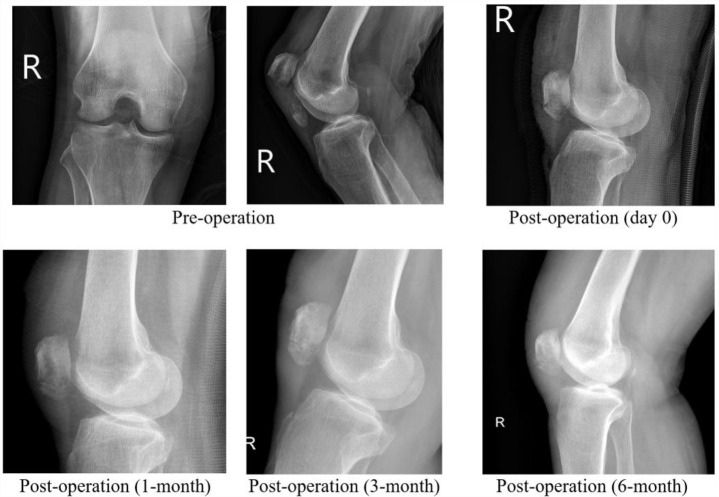

Methods: A retrospective cohort case series was conducted at a single center, involving ten patients with fractures at the lower pole of the patella. Follow-up assessments were performed for a minimum of six months to observe postoperative gap formation and evaluate bony union. Knee motion, pain, function, and any intra- and postoperative complications were documented throughout the follow-up periods.

Results: All patients exhibited complete bone union without gap formation six months postoperatively, accompanied by a regained full range of motion without any functional limitations. No instances of postoperative anterior knee pain, refracture of the inferior patellar pole, or other complications were reported during the follow-up period.